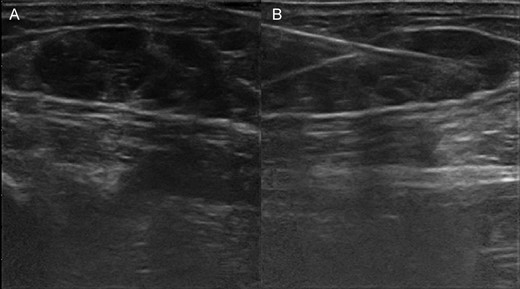

A 61-year-old male patient with no particular previous illnesses was diagnosed with a well-differentiated STMM of the plantar surface of the second toe of the right foot, with infiltrated margins after excisional biopsy. Microscopically, myoepithelioma consists of nests and cords of epithelioid, plasmacytoid or spindle cells, with inconspicuous nucleoli, mainly eosinophilic cytoplasm and, in some cases, clear cells. The cells are embedded in a chondromyxoid, collagenous or hyalinized stroma; no significant nuclear pleomorphism is usually observed and mitoses are scarce. The malignant variant is exclusively recognized by its histological features, showing a marked cytologic atypia, prominent nucleoli, necrosis and a high mitotic index (>7/10 HPF) [2, 5]. The patient underwent computerized tomography (CT) of the chest and abdomen for staging; the results were normal. Considering the residual disease in the previous excision of the nodule, the patient underwent a radical disarticulation of the toe 20 days after excisional biopsy. Three months later, the patient presented a lump on the plantar surface of the third toe of his right foot, a subcutaneous nodule on the right ankle and another nodule on the back of the foot; excisional biopsy of the latter showed de-differentiated STMM. Because of these findings, a positron emission tomography-CT (PET-CT) [7] was performed, which showed the presence of in-transit metastases in the right lower limb, extending to the middle third of the thigh. Ultrasound-guided fine needle aspiration cytology (FNAC) was performed at the level of the most accessible of these lesions, which confirmed secondary STMM (Fig. 1). The patient was then treated with hyperthermic isolated limb perfusion (HILP) using human recombinant tumor necrosis factor 1 mg and melphalan 90 mg. During the subsequent follow-up, a complete response was documented (Figs. 2 and 3).

(A) Ultrasonography shows in-transit metastases by malignant myoepithelioma in the soft tissue of the leg. (B) Performing fine-needle aspiration under ultrasonography guide of the in-transit metastases of the leg.